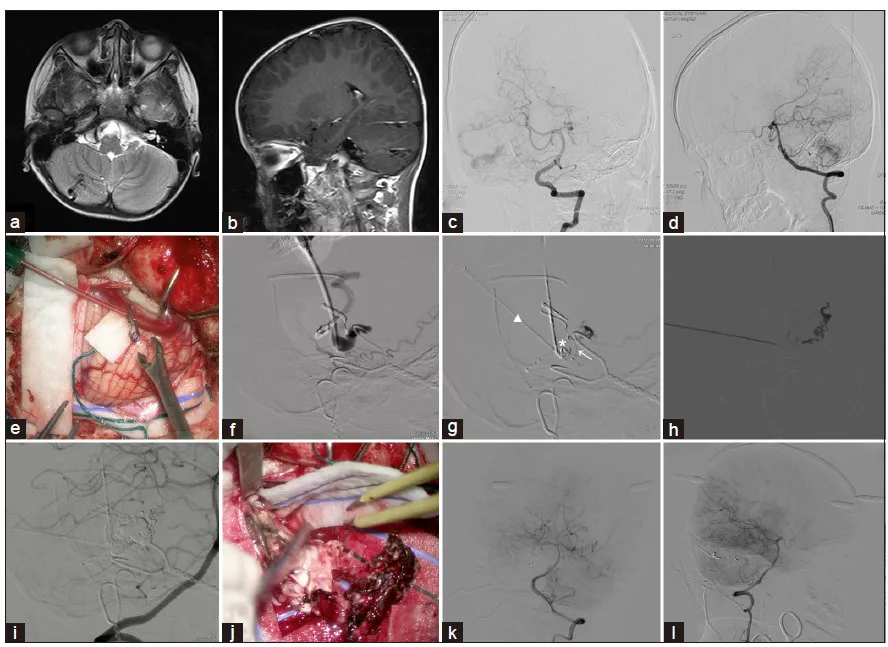

作者介绍1例6岁右侧小脑AVM患儿的治疗。DSA提示bAVM的供血动脉细小而且迂曲,动脉入路难以栓塞。在复合手术室采用DP-SDV技术经静脉入路进行栓塞后,切除畸形血管团(图1)。

图1. 采用DP-SDV技术经静脉栓塞的过程:a.头颅MRI-T2加权轴位相提示,右小脑半球异常血管信号;b.增强MRI-T1加权矢状位相;c.术中DSA椎动脉造影正位片示,bAVM由右侧小脑上动脉(SCA)、小脑前下动脉(AICA)和小脑后下动脉PICA的分支供血,并通过扩张的小脑浅静脉引流至右侧横窦;d.术中DSA椎动脉造影侧位片;e.在显微镜下用18号留置针穿刺目标SDV,拔出套管针后,使用动脉瘤夹固定套管;f.通过套管手推造影剂,造影剂迅速扩散到SDV的下游部分;g.在套管尖端形成胶栓(*),并部分阻塞SDV;因套管头端与畸形团近端尚有距离,术中通过套管将微导管(宽箭头)插入病灶近端;h.在路径图下经微导管注入胶体栓塞剂栓塞AVM,栓塞剂逆行进入供血动脉;i.通过右椎动脉中的导引导管行椎动脉造影,结果提示畸形团次全栓塞;j.显微手术切除bAVM,在病变和正常脑组织之间可见清晰的边界,很容易将畸形血管团从脑组织分离开来;k.术毕DSA椎动脉造影正位片,见bAVM完全消失;l.DSA椎动脉造影侧位片,示bAVM完全消失。